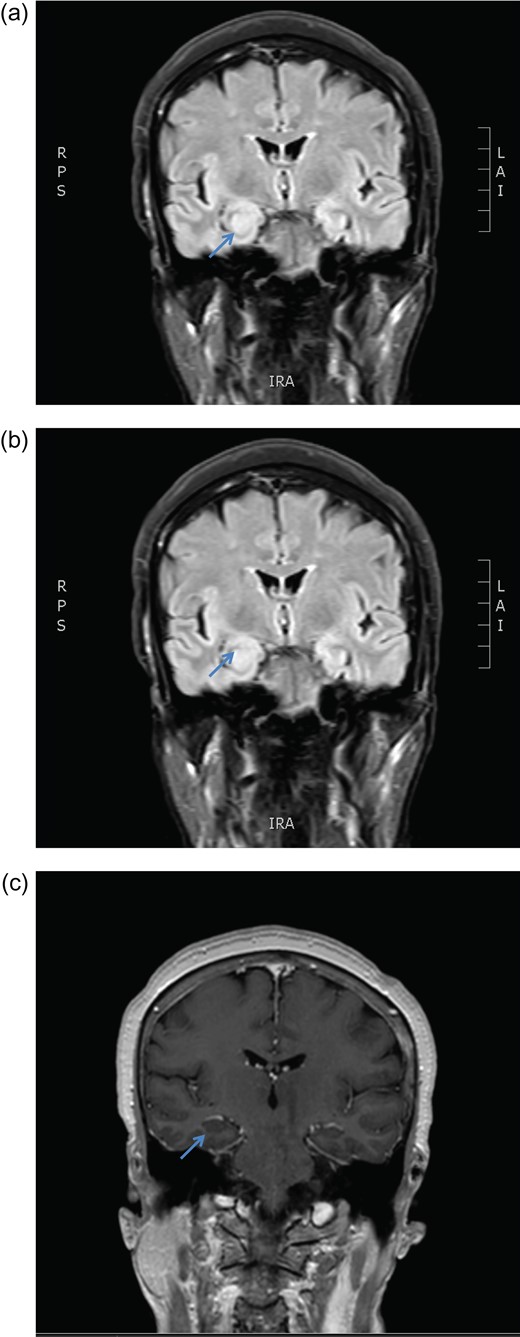

Axial MRI brain (a) diffusion weighted imaging (DWI) and (b) apparent diffusion coefficient (ADC) demonstrating no restricted diffusion.